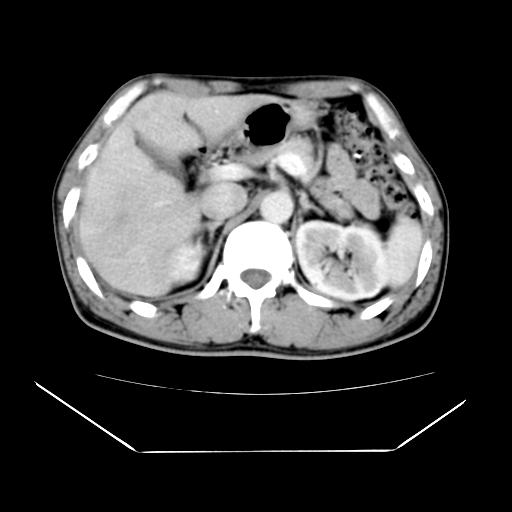

男性,55岁,外院体检afp明显升高,但b超未发现异常,否认乙肝病史。来我院ct增强。有延时扫描。

肝脏右叶动脉期可见低密度影,至延迟期被充填,考虑血管瘤可能性大。

肝右叶病灶

不排除肝右叶肝癌可能。

这个不是肝右静脉吗,这么大的病灶b超不可能发现不了吧

如果这个是癌灶的话则下腔静脉有瘤栓可能

肝6段血管瘤

血管瘤可能性大。

是肝右静脉吧

考虑肝右静脉影。